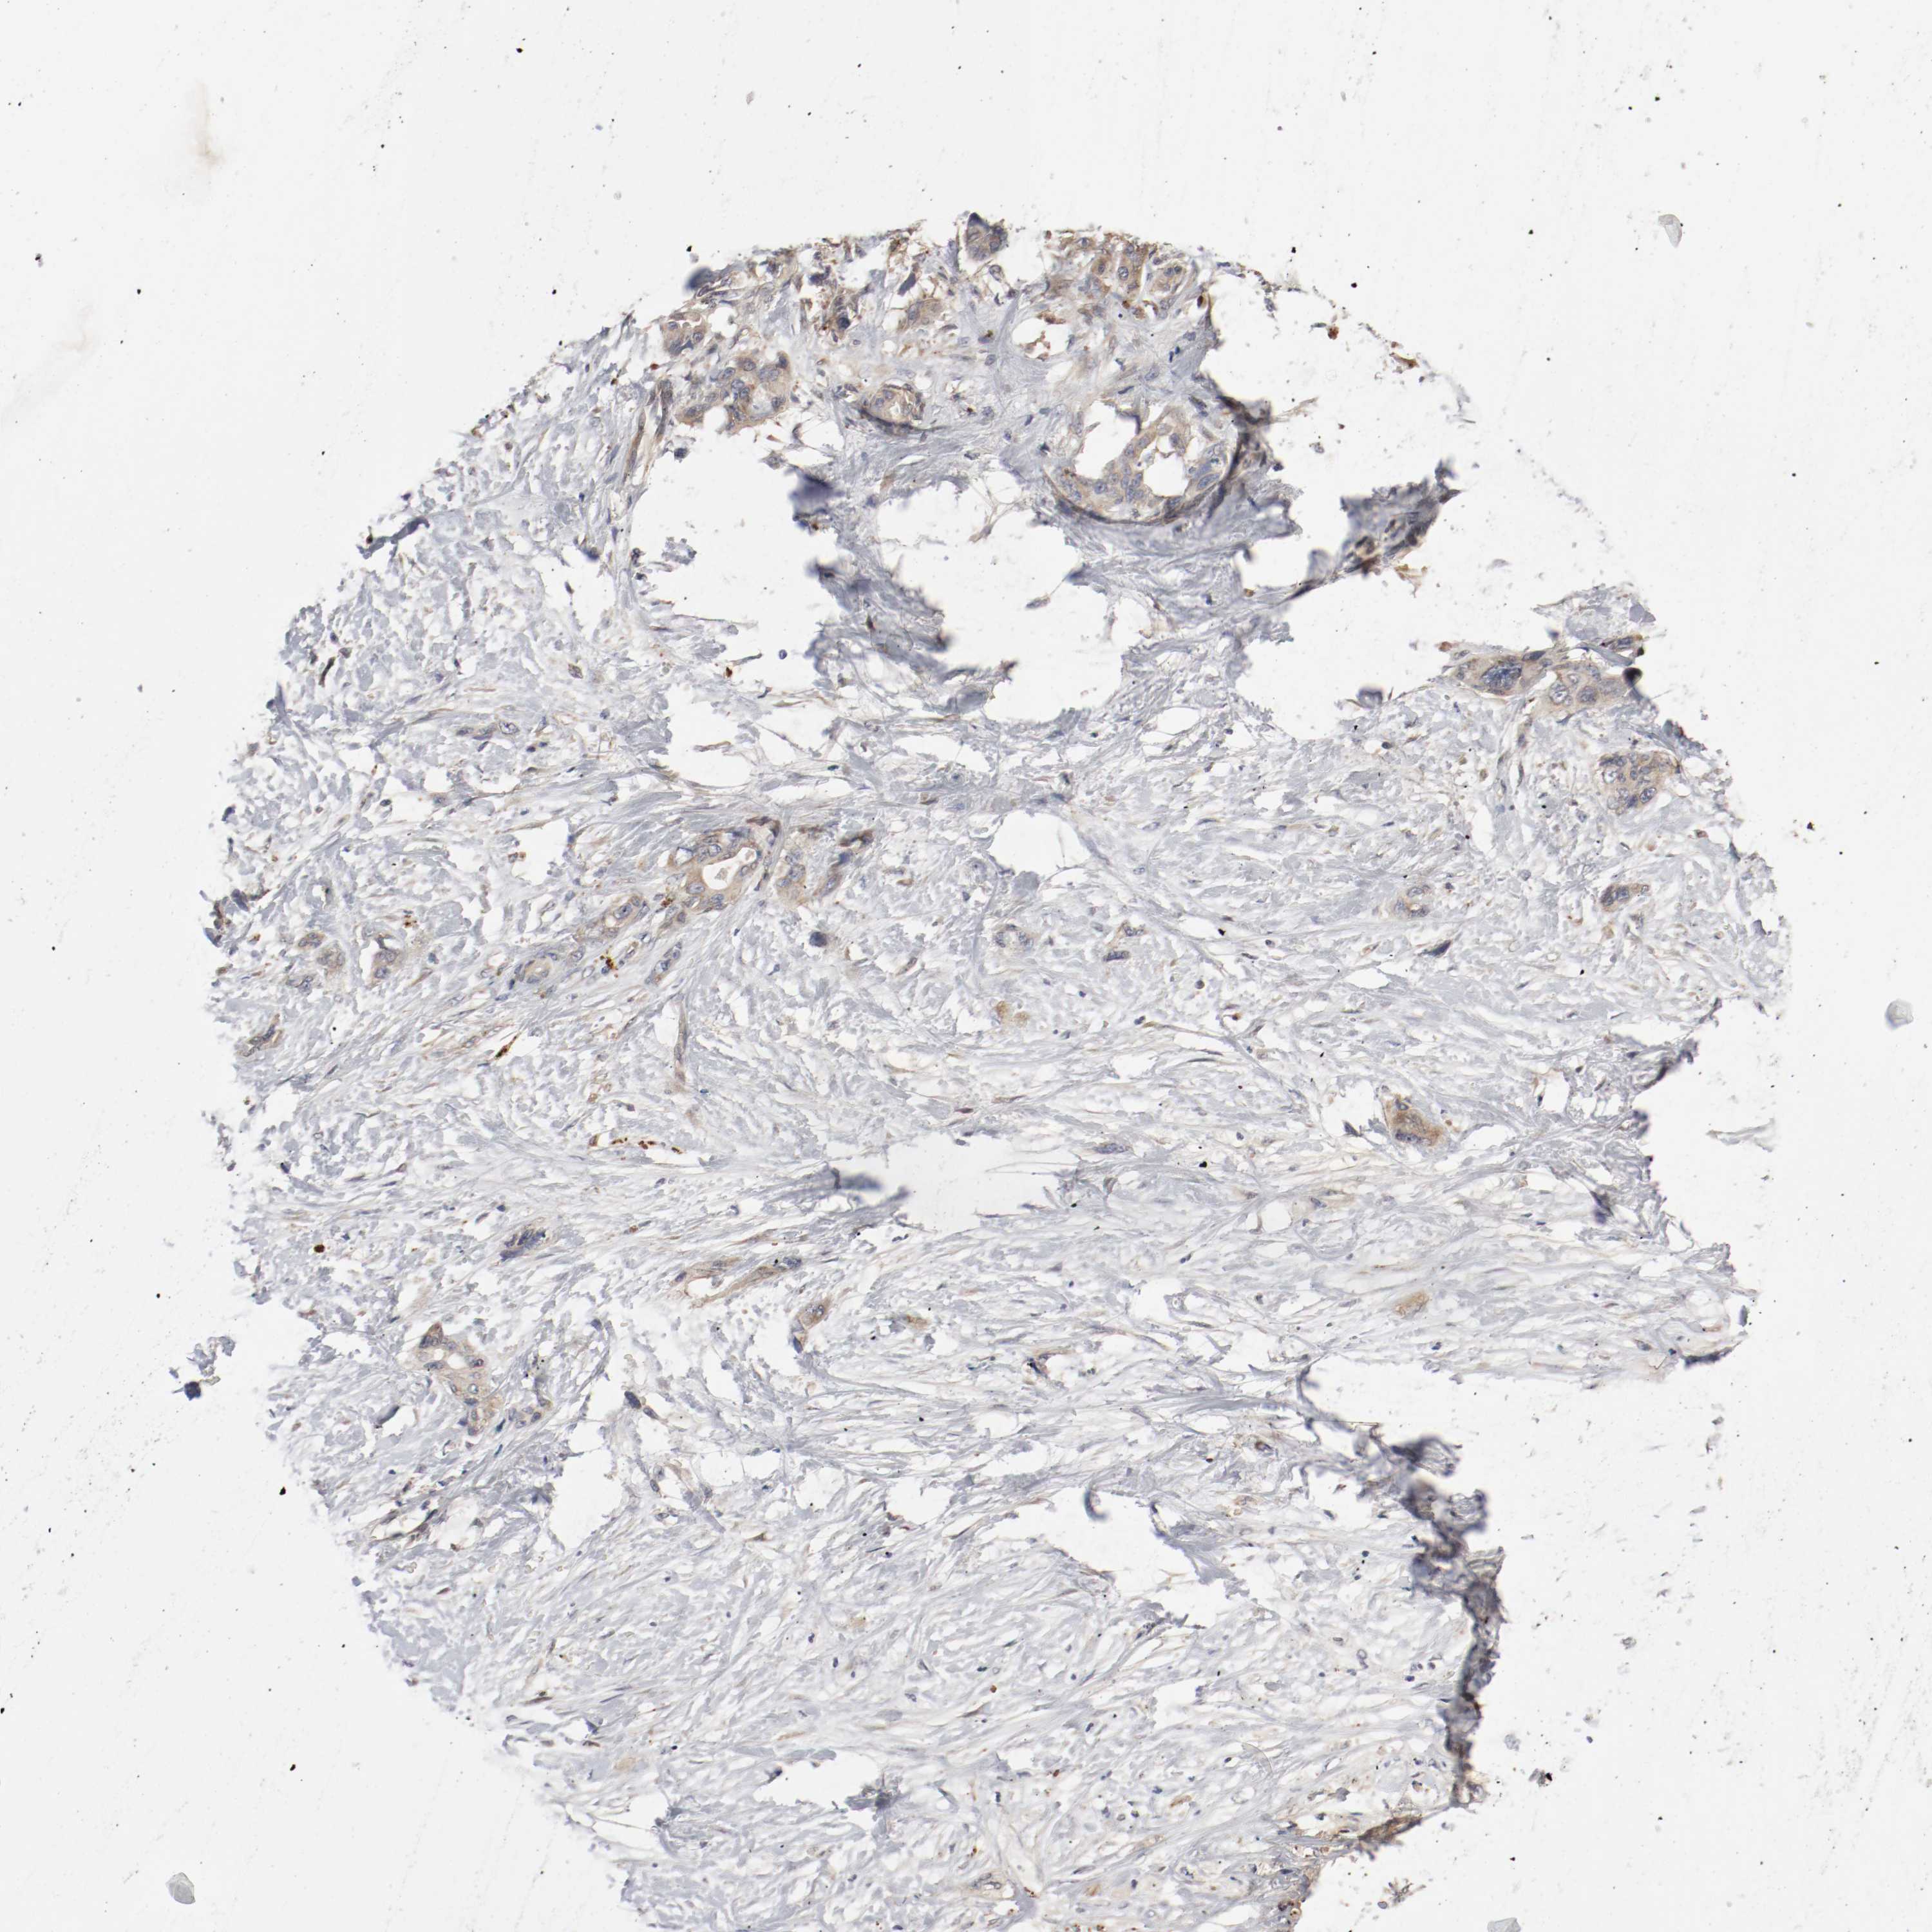

PANCREATIC CANCER - Protein expressioni

A mouse-over function shows sample information and annotation data. Click on an image to view it in a full screen mode. Samples can be filtered based on level of antibody staining by selecting one or several of the following categories: high, medium, low and not detected. The assay and annotation is described here.

Note that samples used for immunohistochemistry by the Human Protein Atlas do not correspond to samples in the TCGA dataset.

Antibody stainingi

Antibody staining in the annotated cell types in the current human tissue is reported as not detected, low, medium, or high, based on conventional immunohistochemistry profiling in selected tissues. This score is based on the combination of the staining intensity and fraction of stained cells.

Each image is clickable and will lead to virtual microscopy that enables deeper exploration of all samples and also displays staining intensity scores, fraction scores and subcellular localization as well as patient and tissue information for each sample.

Antibody HPA005131

Staining

High

Medium

Low

Not detected

Intensity

Strong

Moderate

Weak

Negative

Quantity

>75%

75%-25%

<25%

None

Location

Nuclear

Cytoplasmic/membranous

Cytoplasmic/membranous,nuclear

Adenocarcinoma, NOS

Adenocarcinoma, metastatic, NOS